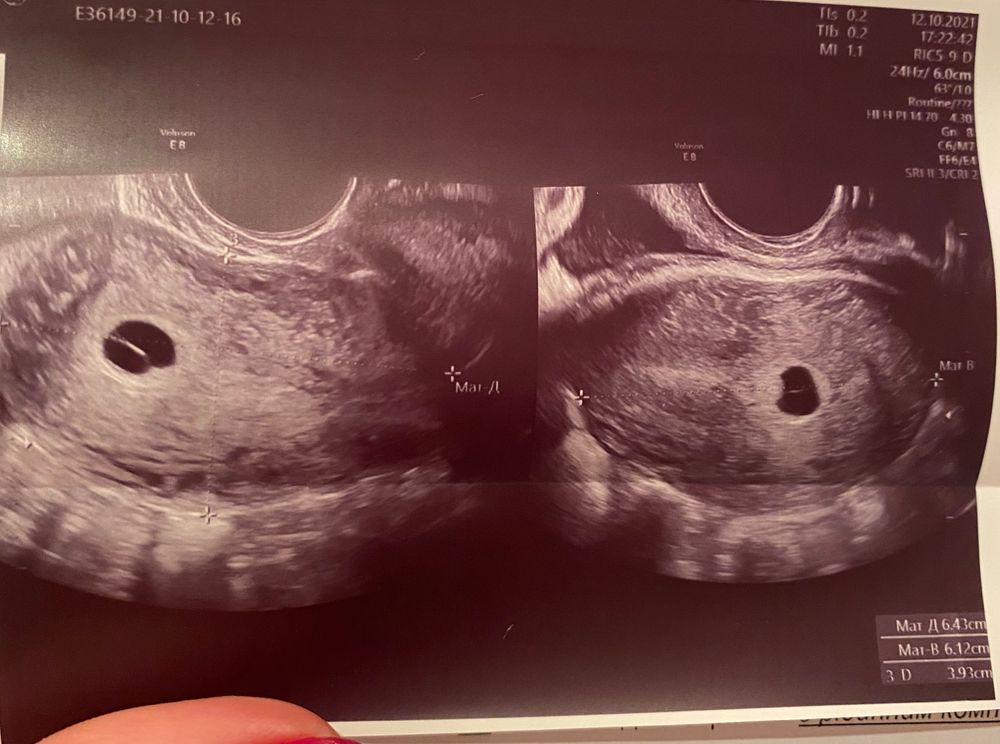

Посмотрите пожалуйста на снимок, у кого была такая же «дырочка» в плодном яйце, что это? Оно пустое, направили на вакуум..

Ой не спешите, подождите. У меня в полости плодного яйца было анэхогенное образование, за которым ничего не было видно. Направляли на вакуум, еле отбилась и выпросила выжидательную тактику, а сама ринулась по узистам, чтоб хотя бы диагноз поставили правильно. Оказалось хорион бамп, а за ним эмбрион. Сейчас все хорошо и я все чаще задумываюсь, чтобв написать пост со снимками узи, вдруг это кому поможет не делать поспешных выводов. На вакуум всегда успеется. Но в это деле лучше не торопиться.

В 6,4 недели у меня только пустое ПЯ было 3 мм, в 7,4 недели уже 9,5 мм, эмбрион и СБ. Просто позже все появилось. Подождите до 16 мм ПЯ.

Sekret , жёлтое тело мне не интересно. Я увидела в вашем заключении узи, что плодное яйцо 8,6 мм - в данный момент врач не может сказать, что это анэмбриония. У меня было плодное яйцо 21 мм и не было ЖМ ( желточного мешка) и меня спокойно отправили ждать неделю. Через неделю все появилось. Ждите и не паникуйте.